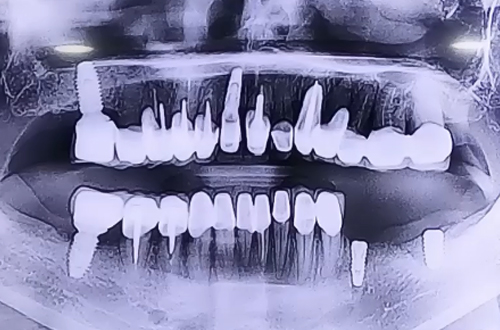

AFTER

치료 유형 아랫니 뼈이식 임플란트

신경 바로 위쪽으로 임플란트 두 개를 안전하게 심으며 양쪽 임플란트를 브릿지 형태로 왼쪽 아래 보철을 완성 시킬 계획입니다.

주변에 뼈이식하신 뼈들이 단단하게 굳는 기간을 기다리셨다가 위 쪽으로 머리 부분 보철을 올리실 때 다음 진료일지로 찾아뵙도록 하겠습니다. ^^!